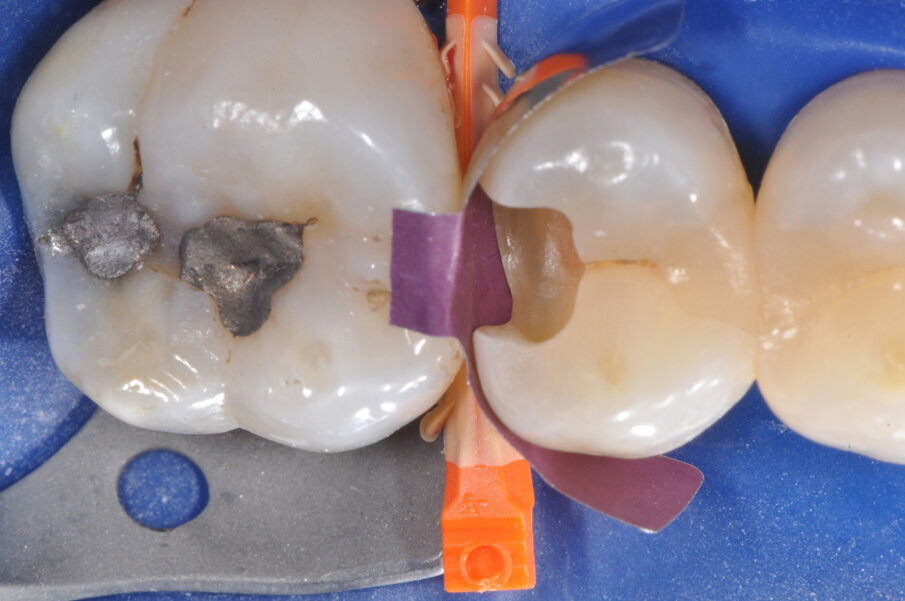

Il caso riguarda l’esecuzione di un restauro interprossimale col sistema di matrici sezionali anelli separatori e cunei Composi-Tight 3D Fusion. Il paziente presenta carie penetrante (D3) a carico dell’elemento 1.5 distale. Viene posizionata la diga di gomma (Fig. 1).

Viene posizionato un cuneo con matrice allo scopo di proteggere il dente aprossimale (Fig. 2). La cavità è stata preparata, la carie asportata, i margini cavitari devono essere rifiniti (Fig. 3). Vengono rimossi il cuneo e la matrice per meglio rifinire il gradino cervicale e per valutare che tipo di cuneo utilizzare (Fig. 4). Ai fini di migliorare l’adattamento della matrice viene utilizzata una striscia abrasiva in plastica di grana media (Fig. 5).